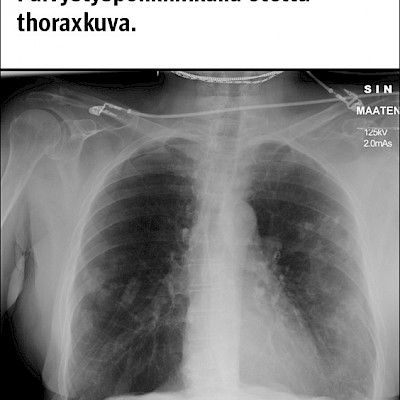

Kasvoja turvottava yskä 55-vuotias rakennusmies hakeutui työterveyslääkärin vastaanotolle kuumeen ja yskän vuoksi. Edellisen kerran hän oli käynyt lääkärissä muutamaa vuotta aiemmin, keuhkoputkentulehduksen vuoksi. Perussairauksia, allergioita, lääkeaineyliherkkyyksiä tai säännöllistä lääkitystä hänellä ei ollut. Tiedossa ei ollut myöskään tuberkuloosialtistusta. Eeva-Maija Nieminen Lehti 35: Koepalat 35/2017 Kommentteja